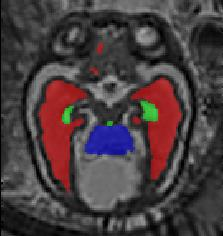

Limiting failures of machine learning systems is of paramount importance for safety-critical applications. In order to improve the robustness of machine learning systems, Distributionally Robust Optimization (DRO) has been proposed as a generalization of Empirical Risk Minimization (ERM). However, its use in deep learning has been severely restricted due to the relative inefficiency of the optimizers available for DRO in comparison to the wide-spread variants of Stochastic Gradient Descent (SGD) optimizers for ERM. We propose SGD with hardness weighted sampling, a principled and efficient optimization method for DRO in machine learning that is particularly suited in the context of deep learning. Similar to a hard example mining strategy in practice, the proposed algorithm is straightforward to implement and computationally as efficient as SGD-based optimizers used for deep learning, requiring minimal overhead computation. In contrast to typical ad hoc hard mining approaches, we prove the convergence of our DRO algorithm for over-parameterized deep learning networks with ReLU activation and a finite number of layers and parameters. Our experiments on fetal brain 3D MRI segmentation and brain tumor segmentation in MRI demonstrate the feasibility and the usefulness of our approach. Using our hardness weighted sampling for training a state-of-the-art deep learning pipeline leads to improved robustness to anatomical variabilities in automatic fetal brain 3D MRI segmentation using deep learning and to improved robustness to the image protocol variations in brain tumor segmentation. Our code is available at https://github.com/LucasFidon/HardnessWeightedSampler.